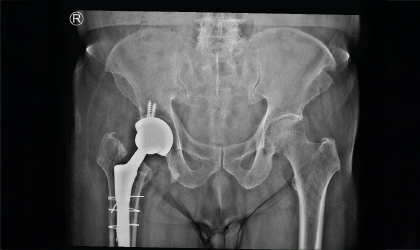

This 83 year old gentle man had a hip fracture 25 years ago. This became painful recently. He had an interesting (to the surgeons!) complication with a fracture of the stem in 3 places. This was revised to a total hip replacement. We used a longer stem to bypass the defects. He is mobile with a stick.

Despite his age and the complexity of the case, the revision surgery was a success. With restored mobility and reduced pain, he enjoys independence in his daily activities.